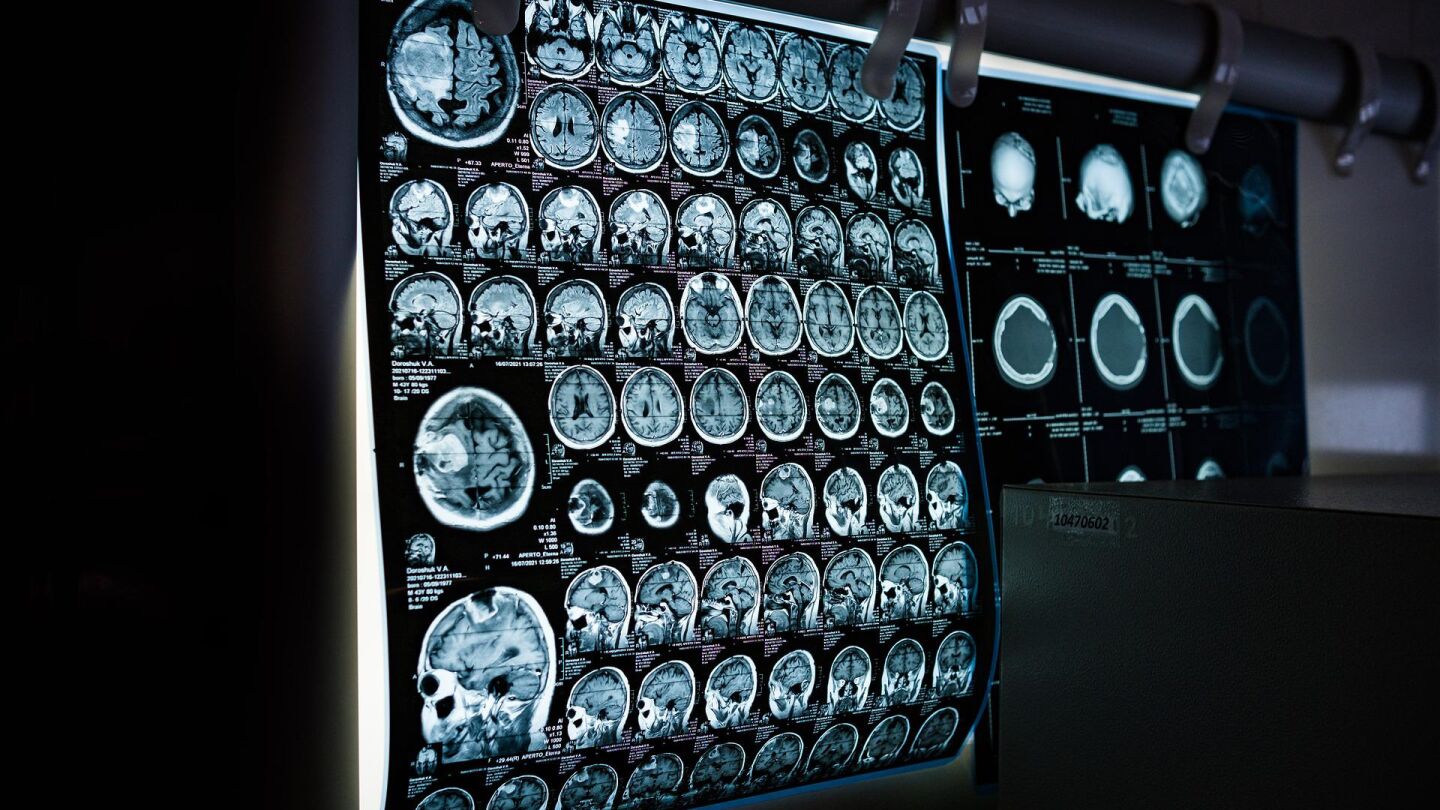

Existen varios tipos de afasia según la parte del cerebro que haya sufrido daños. Esta es la clasificación de Geschwind que recoge la Asociación sin ánimo de lucro Afasia.org.